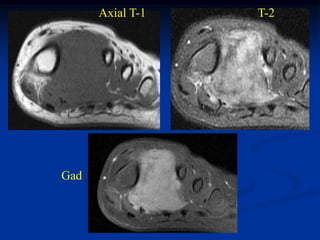

Case #259                   Axial T-1 MRI

72 year male with MFH posterior compartment thigh

Axial T-2 MRI

Case #259 Axial T-1 MRI 72 year male with MFH posterior compartment thigh